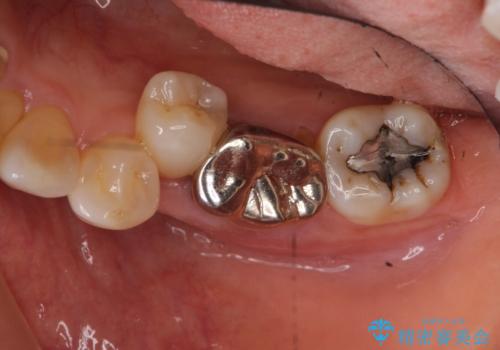

- 63.8万円 左下部分矯正27.5万円 奥歯ブリッジ36.3万円(仮歯1.1万円×3本 ジルコニアクラウン11万円x3本)費用は治療当時の料金となります